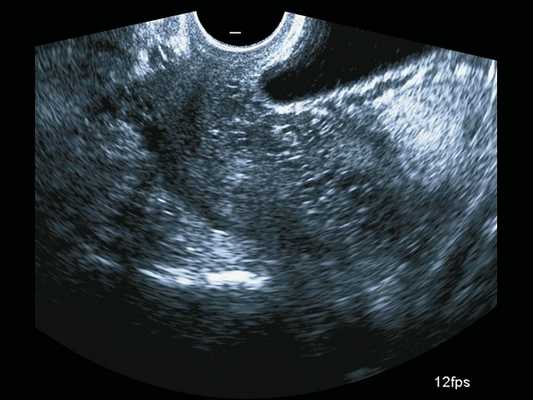

Сканирование в сроке 32 +4 нед беременности проводилось на ультразвуковом сканере премиум-класса W10 (компании Samsung) c использованием конвексного (CA1-7A) и внутриполостного (EV3-10B) датчиков с применением технологии LumiFlow™ (рис. 4-7).

Рис. 6. Беременность 32 +4 нед. Трансвагинальное сканирование: ретроплацентарные лакуны в шейке матки и цервикальном канале.

В режиме серошкального сканирования все ранее идентифицированные особенности плацентации (PAS 3a): ретроплацентарные лакуны, васкулярная инвазия в шейку матки, исчезновение нормальной гипоэхогенной ретроплацентарной зоны, истончение миометрия, выпячивание плаценты, гиперваскуляризация пузырно-маточной зоны были подтверждены.

Дополнительное использование технологии стереоскопической визуализации кровотока (LumiFlow™) позволило визуализировать вовлеченность стенки мочевого пузыря беременной в конгломерат тканей аномальной плацентации (сосудистые мостики (rail sign) из миометрия сквозь серозный покров в стенку мочевого пузыря), то есть идентифицировать placenta percreta (PAS 3b). Проведенная в последующем МРТ констатировала полное предлежание плаценты с прорастанием в рубец, через все слои миометрия, шейку матки и цервикальный канал (рис. 8) и верхнюю стенку мочевого пузыря.